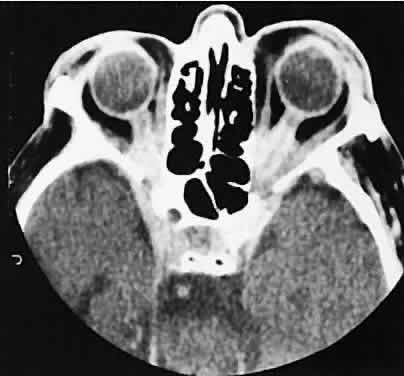

Fig. 10. Optic nerve glioma. Axial section shows lobulated iso-dense enlargement of the optic nerve glioma compared with the intense contrast enhancement and peripheral calcification characteristic of an optic nerve sheath meningioma.